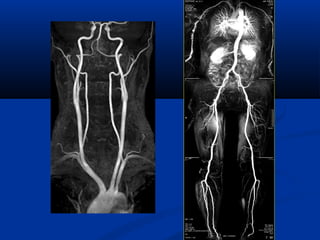

Xaùc ñònh vò tríxöông söôøn treân CT

NOÄI SOI AÛOPHEÁ QUAÛN